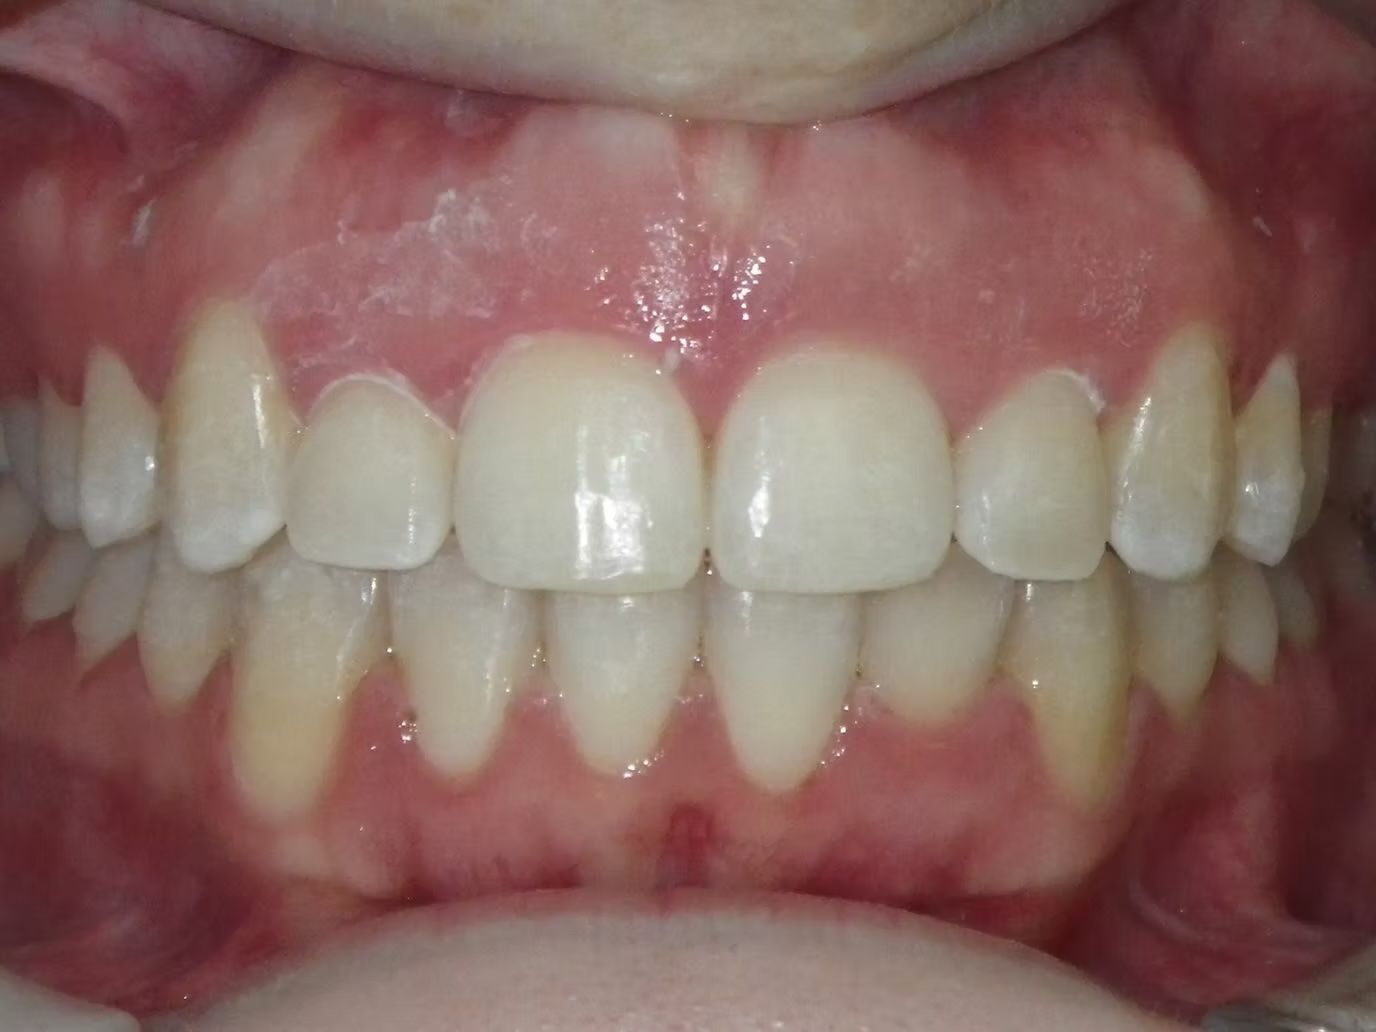

Johntavious

Johntavious didn't like that one of his lower teeth was set behind the rest. He went to many orthodontists who told him to extract the tooth or multiple teeth to correct the alignment. Johntavious and his parents didn't want to go that route and wanted to try to align the teeth without the extraction. Dr. Bret was able to successfully straighten the upper and lower teeth - fit the tooth that was back into the dental arch and make Johntavious and his parents really happy.